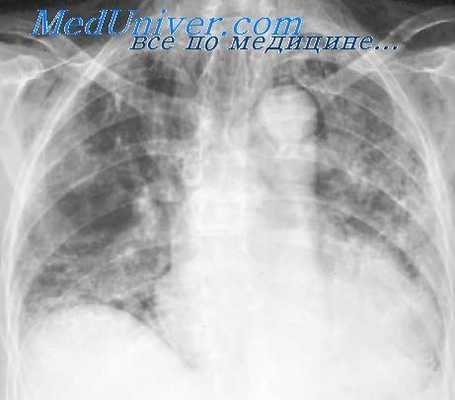

Клинические симптомы послеоперационных пневмоний у больных, перенесших операции на средостении, характеризуются повышением температуры, ухудшением самочувствия, кашлем, вначале без мокроты, а через 4—5 дней с отхаркиванием желтоватой, а иногда с примесью крови мокроты. У ряда больных с двусторонней пневмонией наблюдается цианоз, сильная одышка, тахикардия. Имеет место лейкоцитоз до 10 000—14 000 с левым сдвигом лейкоцитарной формулы, ускорение РОЭ.